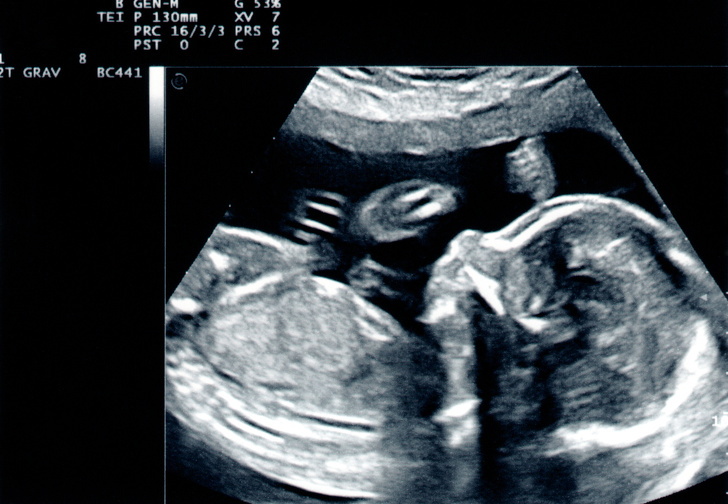

Ми прилетіли з чоловіком в інше місто, де нас зустріла сімейна пара. Їм було важливо познайомитися з нами обома. Ми вирішили поспілкуватися в одному з кафе. Спочатку було трохи ніяково, адже стільки питань треба обговорити при першій зустрічі, а тема дуже делікатна. Але все пройшло добре. Як тільки формальності зважилися, ми поїхали в клініку. Там нас зустріла завідуюча відділенням. Виявилося, що вона наш репродуктолог. Лікар подивилася всі мої аналізи, зробила мені УЗД, і їй все сподобалося. Я була така щаслива — це непередаване відчуття, що ти здатний врятувати чиєсь життя.

Важливо розуміти, що сурогатне материнство не все залежить від самої сурогатної матері. Наприклад, в моєму випадку у биоматери взяли яйцеклітини і «зробили» ембріони, щоправда, вийшло їх зовсім небагато — всього 6 яйцеклітин, і з них тільки 5 ембріонів. Потім ці ембріони проходять генетичний розвиток, в результаті якого вийшло лише 2 ембріона нормальної якості.